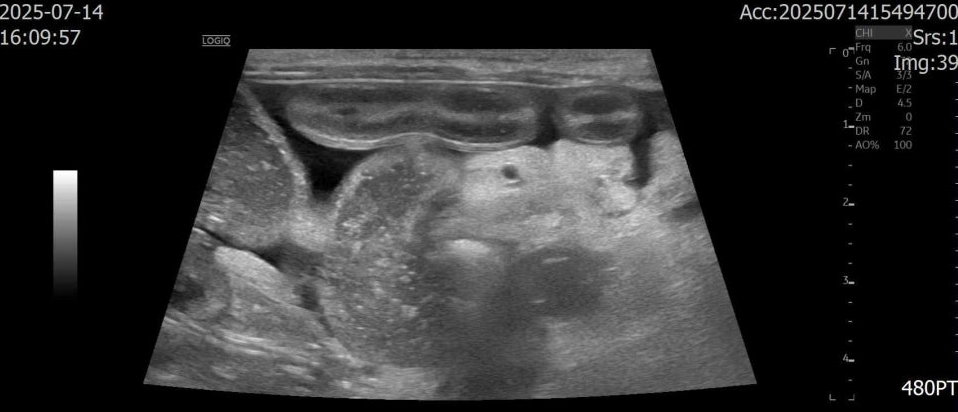

초음파 검사

복부 초음파에서는

- 소장 전반의 점막이 비정상적으로 밝게 보였고,

- 장 점막에 줄무늬 모양의 변화(striation sign)가 반복적으로 관찰되었습니다.

- 장 내에는 액체 저류가 동반되어 있었으며,

- 결장에는 심한 설사 형태의 변이 확인되었습니다.

- 복강 전반에는 중등도의 복수가 존재했고,

- 장 주변 지방 조직에도 염증성 변화가 동반되어 있었습니다.

이러한 소견은 장 점막을 통해 단백질이 지속적으로 소실되고 있는 상태, 즉 단백 소실성 장질환(Protein-losing enteropathy, PLE)을 강하게 시사하는 결과였습니다.

추가로 담낭 내 슬러지와 담낭 및 담도벽의 비후가 확인되었는데, 이는 복수로 인한 부종성 변화와 연관된 소견으로 판단되었습니다.

이상의 검사 결과를 종합하여, 나무는 단백 소실성 장질환(Protein-losing enteropathy, PLE)이 가장 강하게 의심되는 상태로 평가되었습니다.